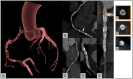

Cardiac computed tomography (CT) was introduced in the late 1990's. Since then, an increasing body of evidence on its clinical applications has rapidly emerged. From an initial emphasis on its technical efficiency and diagnostic accuracy, research around cardiac CT has now evolved towards outcomes-based studies that provide information on prognosis, safety, and cost. Thanks to the strong and compelling data generated by large, randomized control trials, the scientific societies have endorsed cardiac CT as pivotal diagnostic test for the management of appropriately selected patients with acute and chronic coronary syndrome. This consensus document endorsed by the European Association of Cardiovascular Imaging is divided into two parts and aims to provide a summary of the current evidence and to give updated indications on the appropriate use of cardiac CT in different clinical scenarios. This first part focuses on the most established applications of cardiac CT from primary prevention in asymptomatic patients, to the evaluation of patients with chronic coronary syndrome, acute chest pain, and previous coronary revascularization.

Keywords: acute chest pain; chronic coronary syndrome; coronary artery bypass graft; coronary calcium; coronary computed tomography angiography; coronary stent.